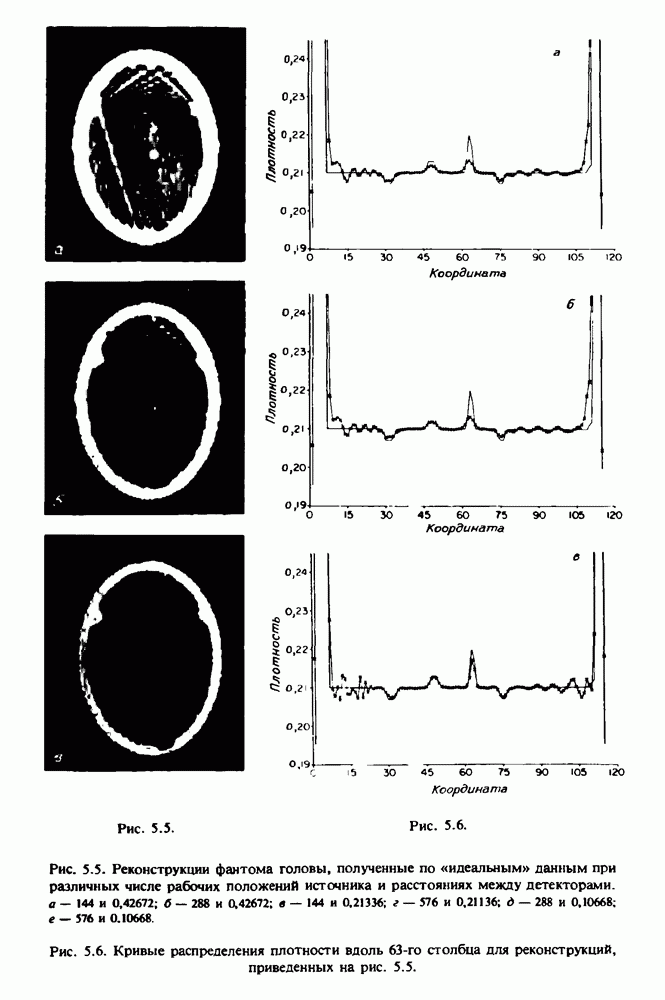

Это явление иллюстрируется также рис. 15.11 и 15.12, где левые изображения получены по серии из 10 срезов толщиной 5 мм, а правые — по серии из 8 срезов толщиной 1,5 мм. На рис. 15.11,а и 15.12,а за основу взяты изображения рис. 15.8 — 15.10, в которых фрагмент из 96 х 96 элементов изображения использовался для идентификации спинного мозга в целом. На рис. 15.11,б и 15.12,б приведены изображения половины спинного мозга, синтезированные по кадрам размерами 48 х 96, занимающим левую

Рис. 15.10. (см. скан) Два последовательных среза толщиной 0,8 мм, полученных путем интерполяции данных по срезам толщиной 5 мм. Данные изображения соответствуют рис. 15.9. Изображение спикулы полностью не воспроизводится на рис. 15.10,б из-за эффекта частичного заполнения объема.

часть первоначального полного кадра размером 96 х 96. При этом можно одновременно наблюдать как внутренние, так и внешние структуры мозга при различной его ориентации. Это показано на рис. 15.11 и 15.12, на которых приведены две серии кинокадров, демонстрирующих изображения спинного мозга при четырех синхронно измененных положениях пациента.